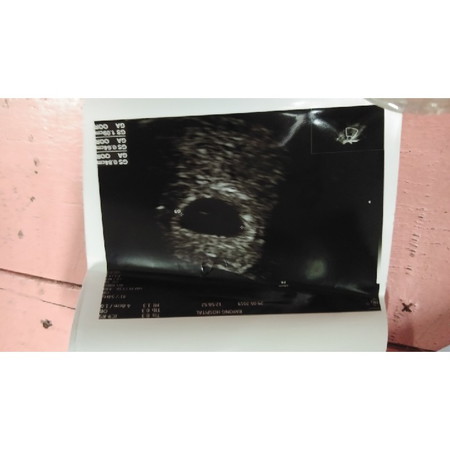

29 วันนี้หมอนัด เจาะเลือด แล้วหมอบอกว่าฮอร์โมนขึ้นสูง ก็คือท้องและ แต่วันนี้หมออัลตร้าซาวด์ช่องคลอดแล้วบอกว่าตอนนี้หมอเจอถุงตั้งครรภ์แล้วแต่ยังไม่เจอตัวน้อง แต่ช่วงนี้เรามีอาการแพ้ท้องแล้วกินน้อยมากน้ำกนักลง3โลอ้วกบ้างกินบ้าง หมอบอกว่านัดอีกที 6มิ.ย.62 มาอัลตร้าซาวด์ช่องคลอดใหม่ว่าจะเจอน้องหรือเปล่าถ้าไม่เจอก็อาจจะเป็นท้องลม ตอนนี้กงวลมากกลัวน้องไม่มาเพราะตั้งใจว่าจะมีน้อง (ปล ครั้งที่แล้วอัลตร้าซาวด์ช่องคลอดแล้วไม่เจอถุงตั้งครรภ์) แต่ครั้งนี้เจอถุงตั้งครรภ์แล้วรอลุ่น 6 มิ.ย ค่ะ